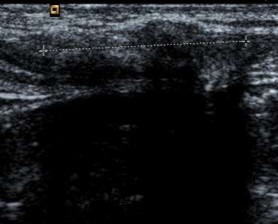

Hình 3.1. Hình ảnh siêu âm mô xơ ở vùng bẹn phải, xuất hiện đường tăng âm với bóng đen cản âm ở phía sau. Bệnh nhân: Ngô Tá Tr 69 tuổi, Nam.

Bảng 3.27. Phân bố độ dày mô xơ của tấm lưới dưới siêu âm

Số trường hợp | Tỉ lệ (%) | |

Mô xơ dày | 121 | 100 |

Mô xơ mỏng | 0 | 0 |

Tổng | 121 | 100 |

Độ dày mô xơ | 2,51 ± 0,21 mm | 2,1 - 3,5 mm |

Bảng 3.28. Phân bố vị trí tấm lưới dưới siêu âm

Nằm ngay ống bẹn | 121 | 100 |

Di lệch, di chuyển | 0 | 0 |

Mô xơ tạo thành quanh tấm lưới nằm ở vùng bẹn 100%, không có di chuyển và di lệch.